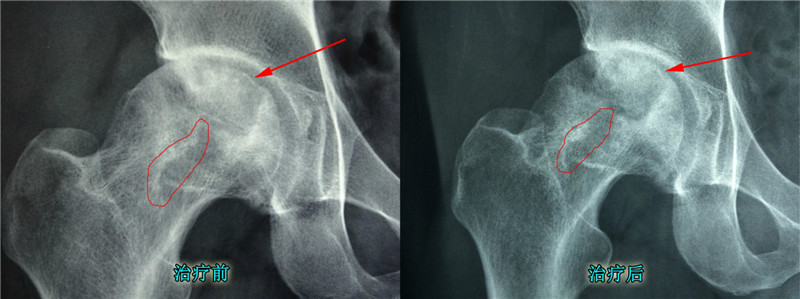

经过4个月的治疗:疼痛症状减轻,塌陷状况改善,骨质恢复

局部对比图:骨质恢复明显